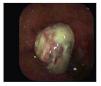

Paciente masculino de 78 años de edad sin antecedentes de importancia que refiere padecimiento de 3 meses de evolución con sensación de masa anal, que refiere prolapso al momento de la defecación. A la exploración se encuentra región perianal normal, no evidencia de lesiones, al realizar tacto rectal se palpa lesión de aproximadamente 2 cm de diámetro que se encuentra en el conducto anal y se evidencia al hacer anoscopia, la lesión protruye al momento de realizar maniobra de Valsalva (Foto 1), motivo por el cual se decide llevar a cabo rectosigmoidoscopia para evaluar la lesión y toma de biopsias (Foto 2) reportándose hallazgos histológicos con relación a melanoma maligno, se inicia estudio de extensión con TAC y radiografía de tórax libres de enfermedad metastásica. En decisión conjunta con los familiares y el deseo del paciente al no contar con un estoma definitivo, se decide hacer resección amplia de la lesión con adecuada evolución del paciente y control de los síntomas. En el estudio histopatológico de la pieza se corroboró el diagnóstico de melanoma anal, reportándose bordes quirúrgicos libres. Hasta su cita de control a la consulta 8 meses posteriores a la cirugía el paciente continúa libre de enfermedad.

Foto 1. Melanoma de conducto anal prolapsado al realizar maniobra de Valsalva.